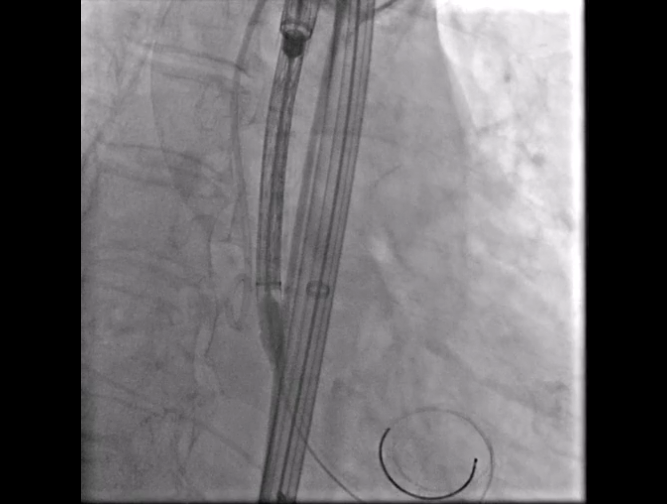

Step 2.建立大鞘通路:大鞘通过升主、边进入边加弯,避免剐蹭弓部斑块

14.gif

15.gif